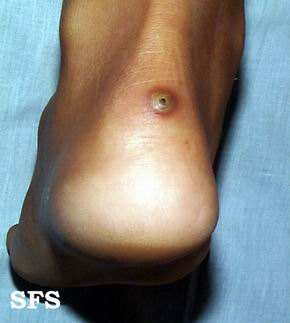

潜蚤病(沙蚤、钻潜蚤)的人体皮肤寄生

潜蚤又称“沙蚤”,在拉丁美洲称穿皮潜蚤,是一种小型的圣类,可寄生于人体皮下,引起潜蚤病。在我国已知有两种潜蚤,一种为盲潜蚤,无眼,寄生在鼠类身体的前端,尤其是耳翼处,故